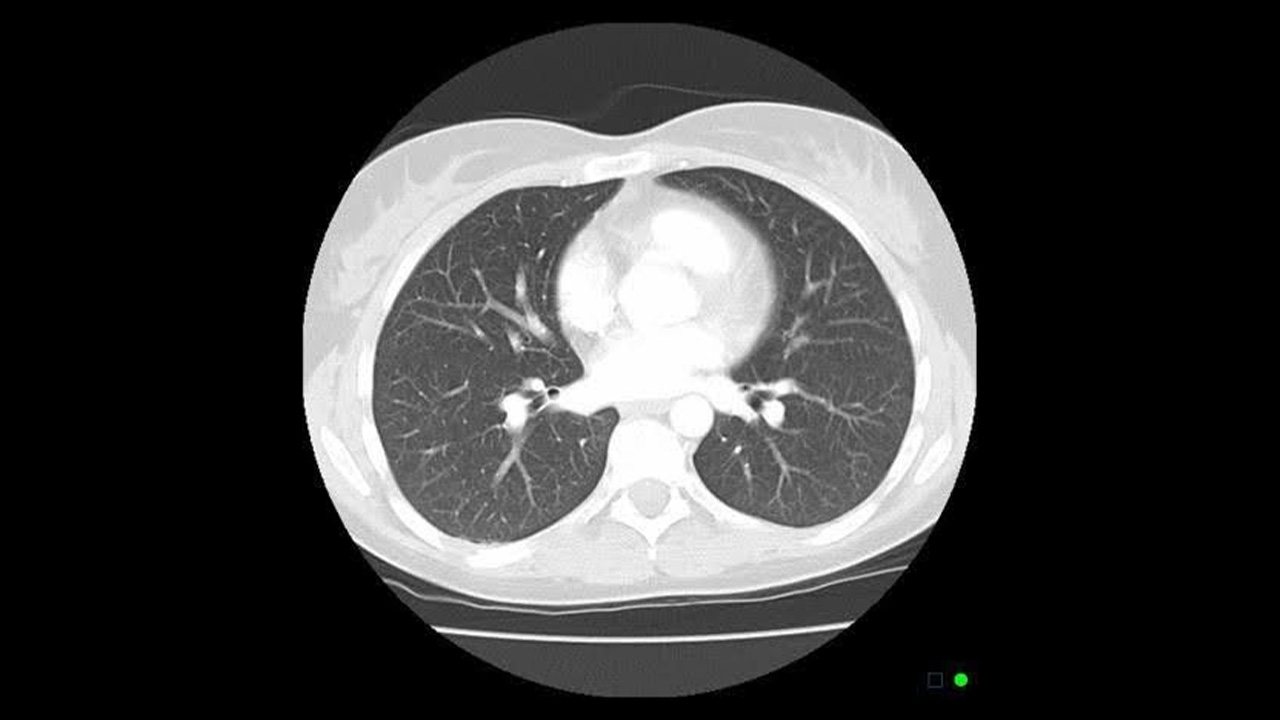

Lung Cancer Screening with Low-Dose CT (LDCT): Who Needs It, Benefits, Risks, and What to Expect

Overview Lung cancer screening with low-dose CT (LDCT) is one of the most powerful tools